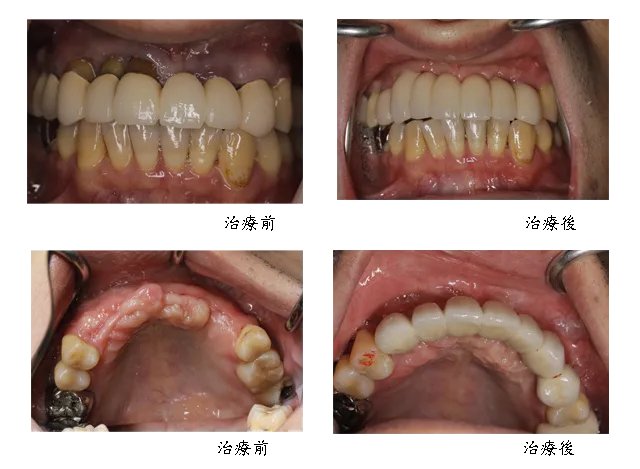

[ 賴先生植牙案例 ]